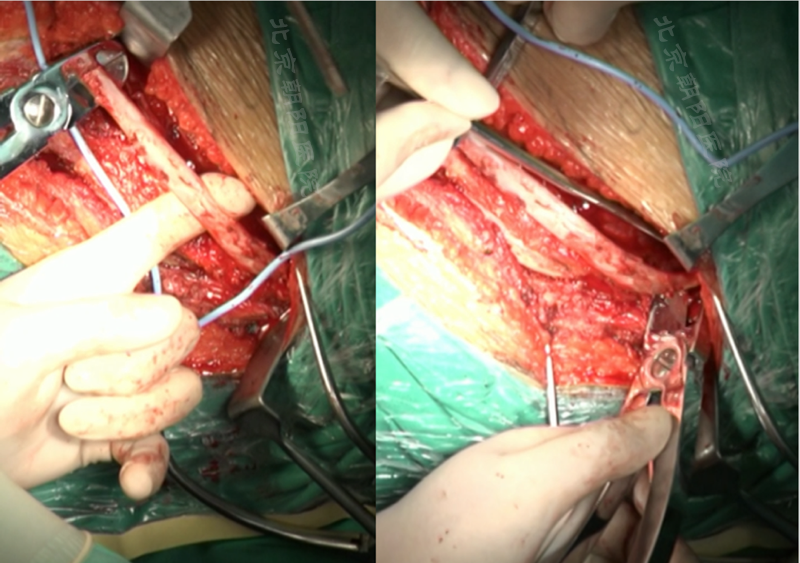

内固定选择的是5.5mm双棒系统,先置入顶椎的螺钉垫板。

置入顶椎的椎体螺钉,螺钉可置入椎体中部到后方1/3之间的范围内。

使用双棒系统时,先置入背侧的螺钉,螺钉指向椎体中线,后置入腹侧的螺钉,螺钉轻度指向后侧。形成对椎体的三角形抓持力。